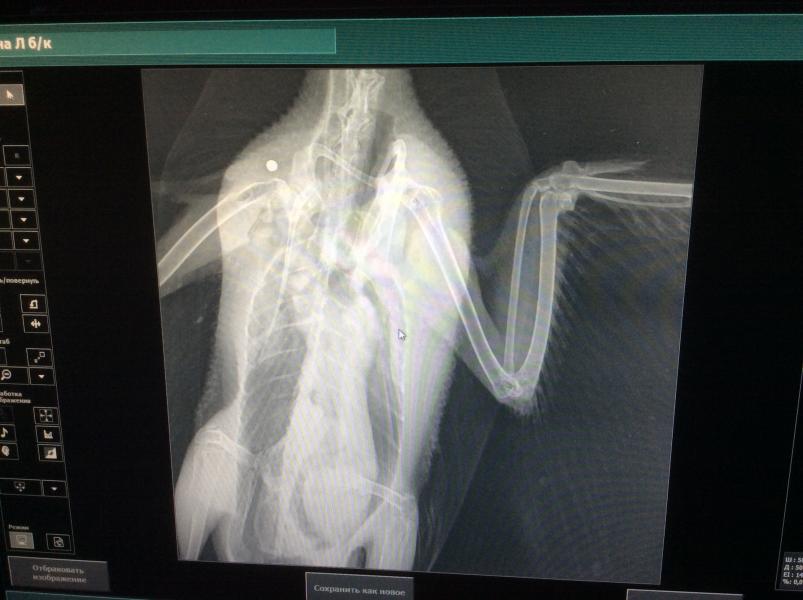

Девочки😭🤦🏼♀️😭😭это боль просто,селезень абсолютно здоров. На лапки он падает потому что истащён и в одной из лап прямо в суставе была пуля((!Врач сказала что сезон охоты давно закрыт,а когда стала извлекать пули,с первой же оказалось что они пластиковые,пластиковая дробь и на это оружие требуется разрешение,поэтому это не дети. Бедный уть,столько пережил😰🙈начало истории с селезнем в предыдущем посте. Все мои страхи по поводу птицы были глупы и не обоснованы. Во первых птичьи всякие глисты человеку не передаются потому что температура человеческого тела ниже чем температура птиц и мы этим гельминтам просто не пригодны для жизни. Во вторых орнитоз которым всех пугают,человеку конечно может передаться,но при условии если вы будете целовать и дотрагиваться до слизистых,до глаз например ну и не будете мыть руки. А саломанелёз это вообще болезнь «грязных рук» и зацепить его можно не только от птиц впрямую. Главное тщательно и почаще мыть руки. И то ничего из этого у утя не обнаружено,нет в помёте даже простейших. В общем полностью здоровый молодой птиц,которого нужно кормить и лечить прооперирована лапку. Если вдруг вам встретится погибающая на морозе птичка не проходите мимо,а я могу подсказать куда её пристроить!